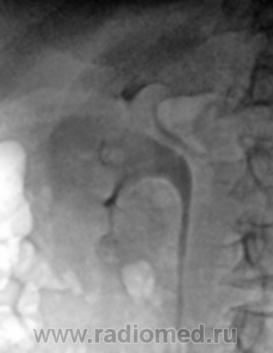

Если вы про это:

Изображение

То это наложение кишечного содержимого, ни каких признаков нет на удвоение почек.